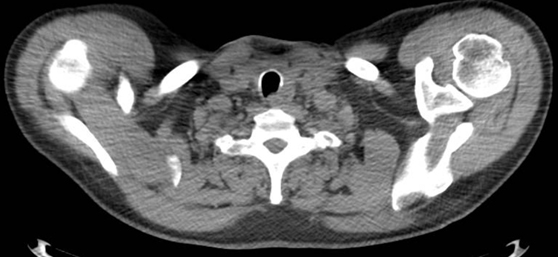

Figure 1. The crescent trachea sign (CT scan)